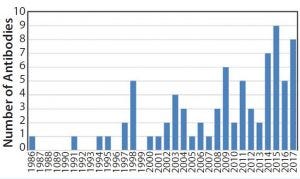

Increasing Number of Monoclonal Antibody Approvals

Figure 5: Approval of antibody products 1986–2017

By the 1990s, we had taken about 20 different MAbs from our research laboratory into the clinic. In 1997 and 1998, several chimeric and the first humanized antibodies were approved (Table 1). Campath-1H was approved in 2001, shortly followed by Humira™ (adalimumab). So far, the year 2017 appears to be setting a record in MAb approvals, with about eight approvals so far and perhaps more by year end (Figure 5).